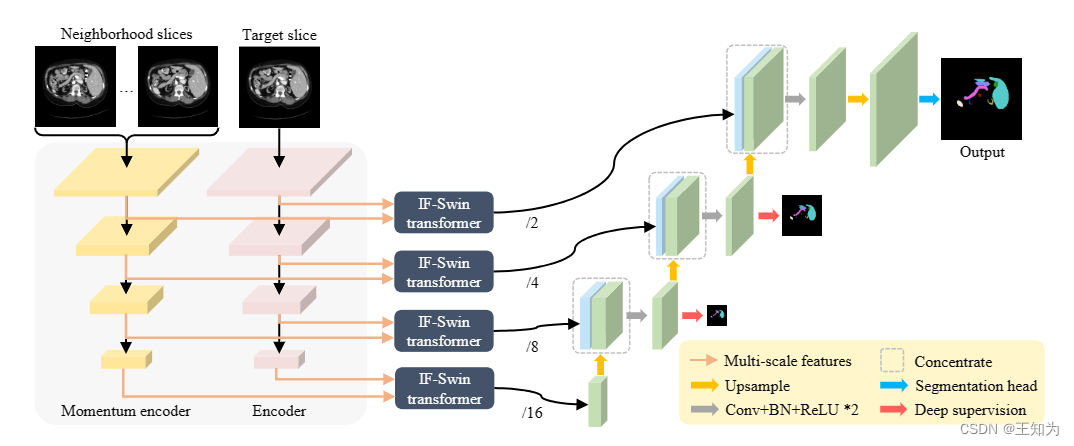

图2. MOSformer的架构。它由双编码器组成:动量编码器用于提取相邻切片信息,而编码器用于提取目标切片信息。IF-Swin transformer被设计用于在多尺度特征上实现切片间的融合。之后,融合后的特征被馈送到CNN解码器,生成目标切片的分割地图。